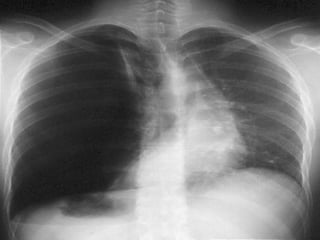

a- RX du thorax :

   Résultats :

Confirmation :

Hyperclareté homogène, avasculaire, périphérique,

Moignon hyperdense rétracté sur le hile,

Distension des EIC et une netteté anormale des cotes.

Plèvre viscérale :fin liseré opaque net comme tracé au

crayon.

Signes radiologiques associés :

* hydro pneumothorax.

*h

hcœur et du médiastin refoulés.

* Anomalies parenchymateuses homo ou

controlatérales.

* Un aspect de petit cœur dans les formes

bilatérales.